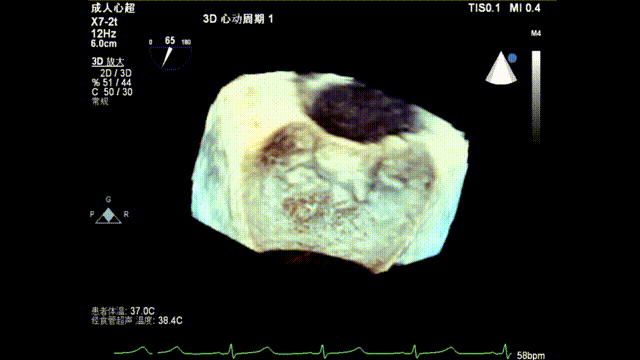

术前超声评估

前瓣长度:26mm;后瓣长度:11mm;二尖瓣后叶牵拉,前、后瓣叶对合深度:9.7mm;对合高度4.4mm;瓣叶及瓣环无钙化,二尖瓣有效开口面积 4.6cm²。诊断重度功能性二尖瓣反流FMR。

术前TEE显示重度功能性二尖瓣反流,反流位于A2/P2;